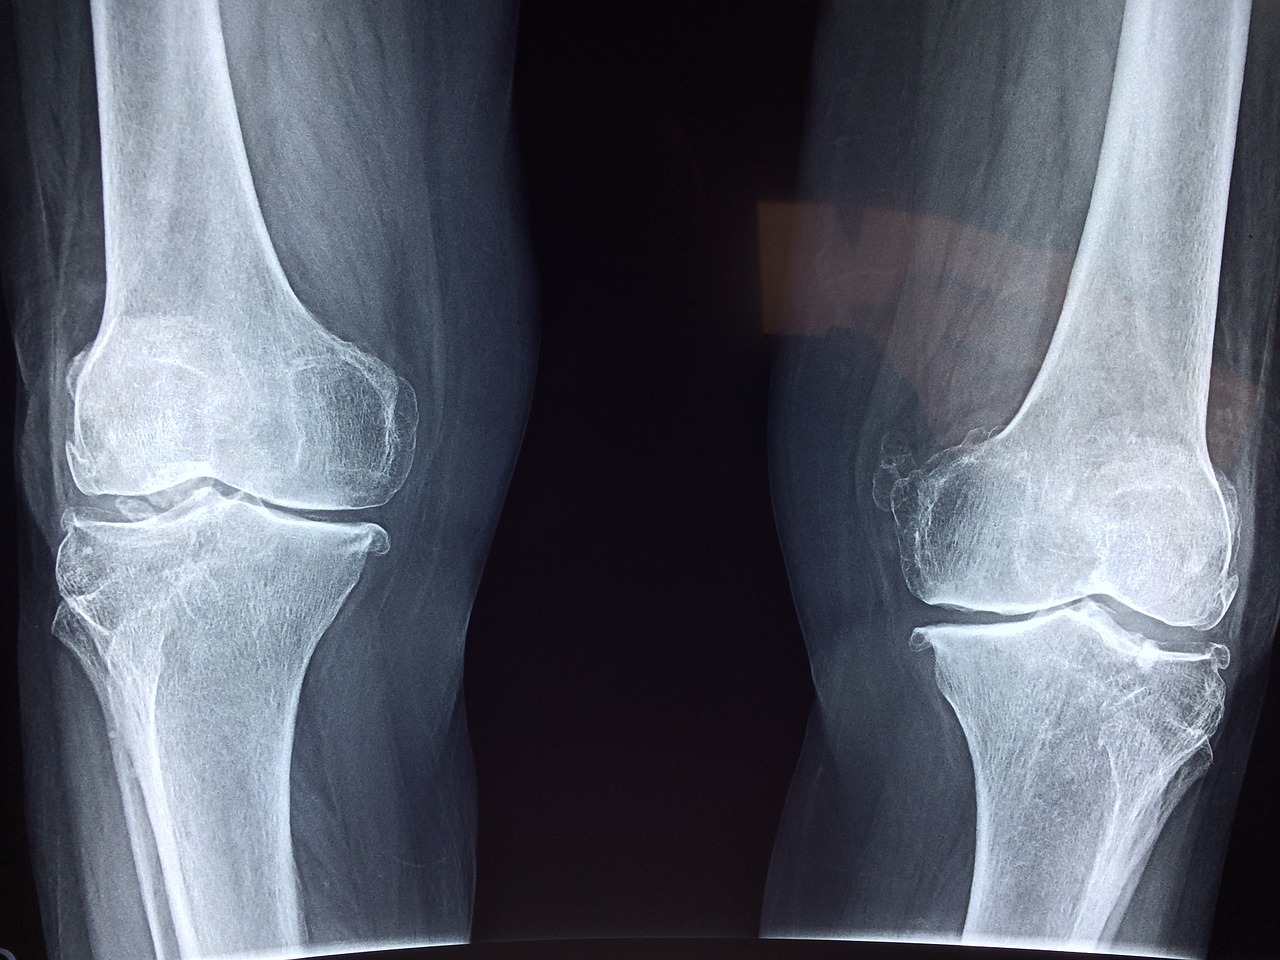

흔히 뼈주사라고 부르는 주사는 뼈에 놓는 주사가 아닙니다. 뼈에 직접적으로 놓는 주사는 수술실에서 시술하는 VP(VertebroPlasty), 혹은 아이들 혈관 없을 때 뼈의 골수 쪽에 수액이나 수혈을 주는 주사를 말합니다. 뼈주사라는 것은 관절염이나 통증이 있는 부위에 신경차단술 주사를 맞는 것을 말합니다. 이 주사를 맞으면 뼈가 삭는다, 뼈가 약해진다, 뼈가 녹는다라고 하여 뼈주사란 별명이 붙었는데요, 사실은 근거가 없는 말입니다! 대부분의 신경차단술에는 스테로이드를 쓰는데 많이 맞으면 뼈를 약하게 만든다고 와전이 되어 많은 사람들이 오해를 합니다. 보통 약물에 유지속 효과나 용량을 적절하게 맞으면 거의 영향을 주지 않습니다.

확실히 스테로이드를 고용량으로 장기적으로 쓰게 되면 골밀도에 영향을 줄 수 있습니다. 그에 관한 논문도 있습니다. 하지만 신경치료할 때 쓰는 약들은 고용량으로 쓰지 않기 때문에 골밀도에 거의 영향을 미치지 않습니다. 류마티스 관절염이나 여러 관절염, 근육통에 스테로이드를 쓰지만 골밀도에 영향을 줄 정도의 용량이 들어가지 않기 때문에 상관이 없습니다. 거기다 매일 맞는 것도 아니고 가끔 주사를 맞는 정도라면 뼈건강에 영향을 주지 않는다고 하네요~ 스테로이드를 과량으로 장기간 쓴다면 뼈에 영향을 줄 수 있지만 잘 조절해서 쓰면 오히려 만성 통증을 줄여주어 생활을 더 윤택하게 만들어 준다고 합니다. 이제 뼈가 녹을 걱정 없이 신경차단술을 받으시면 되겠습니다~